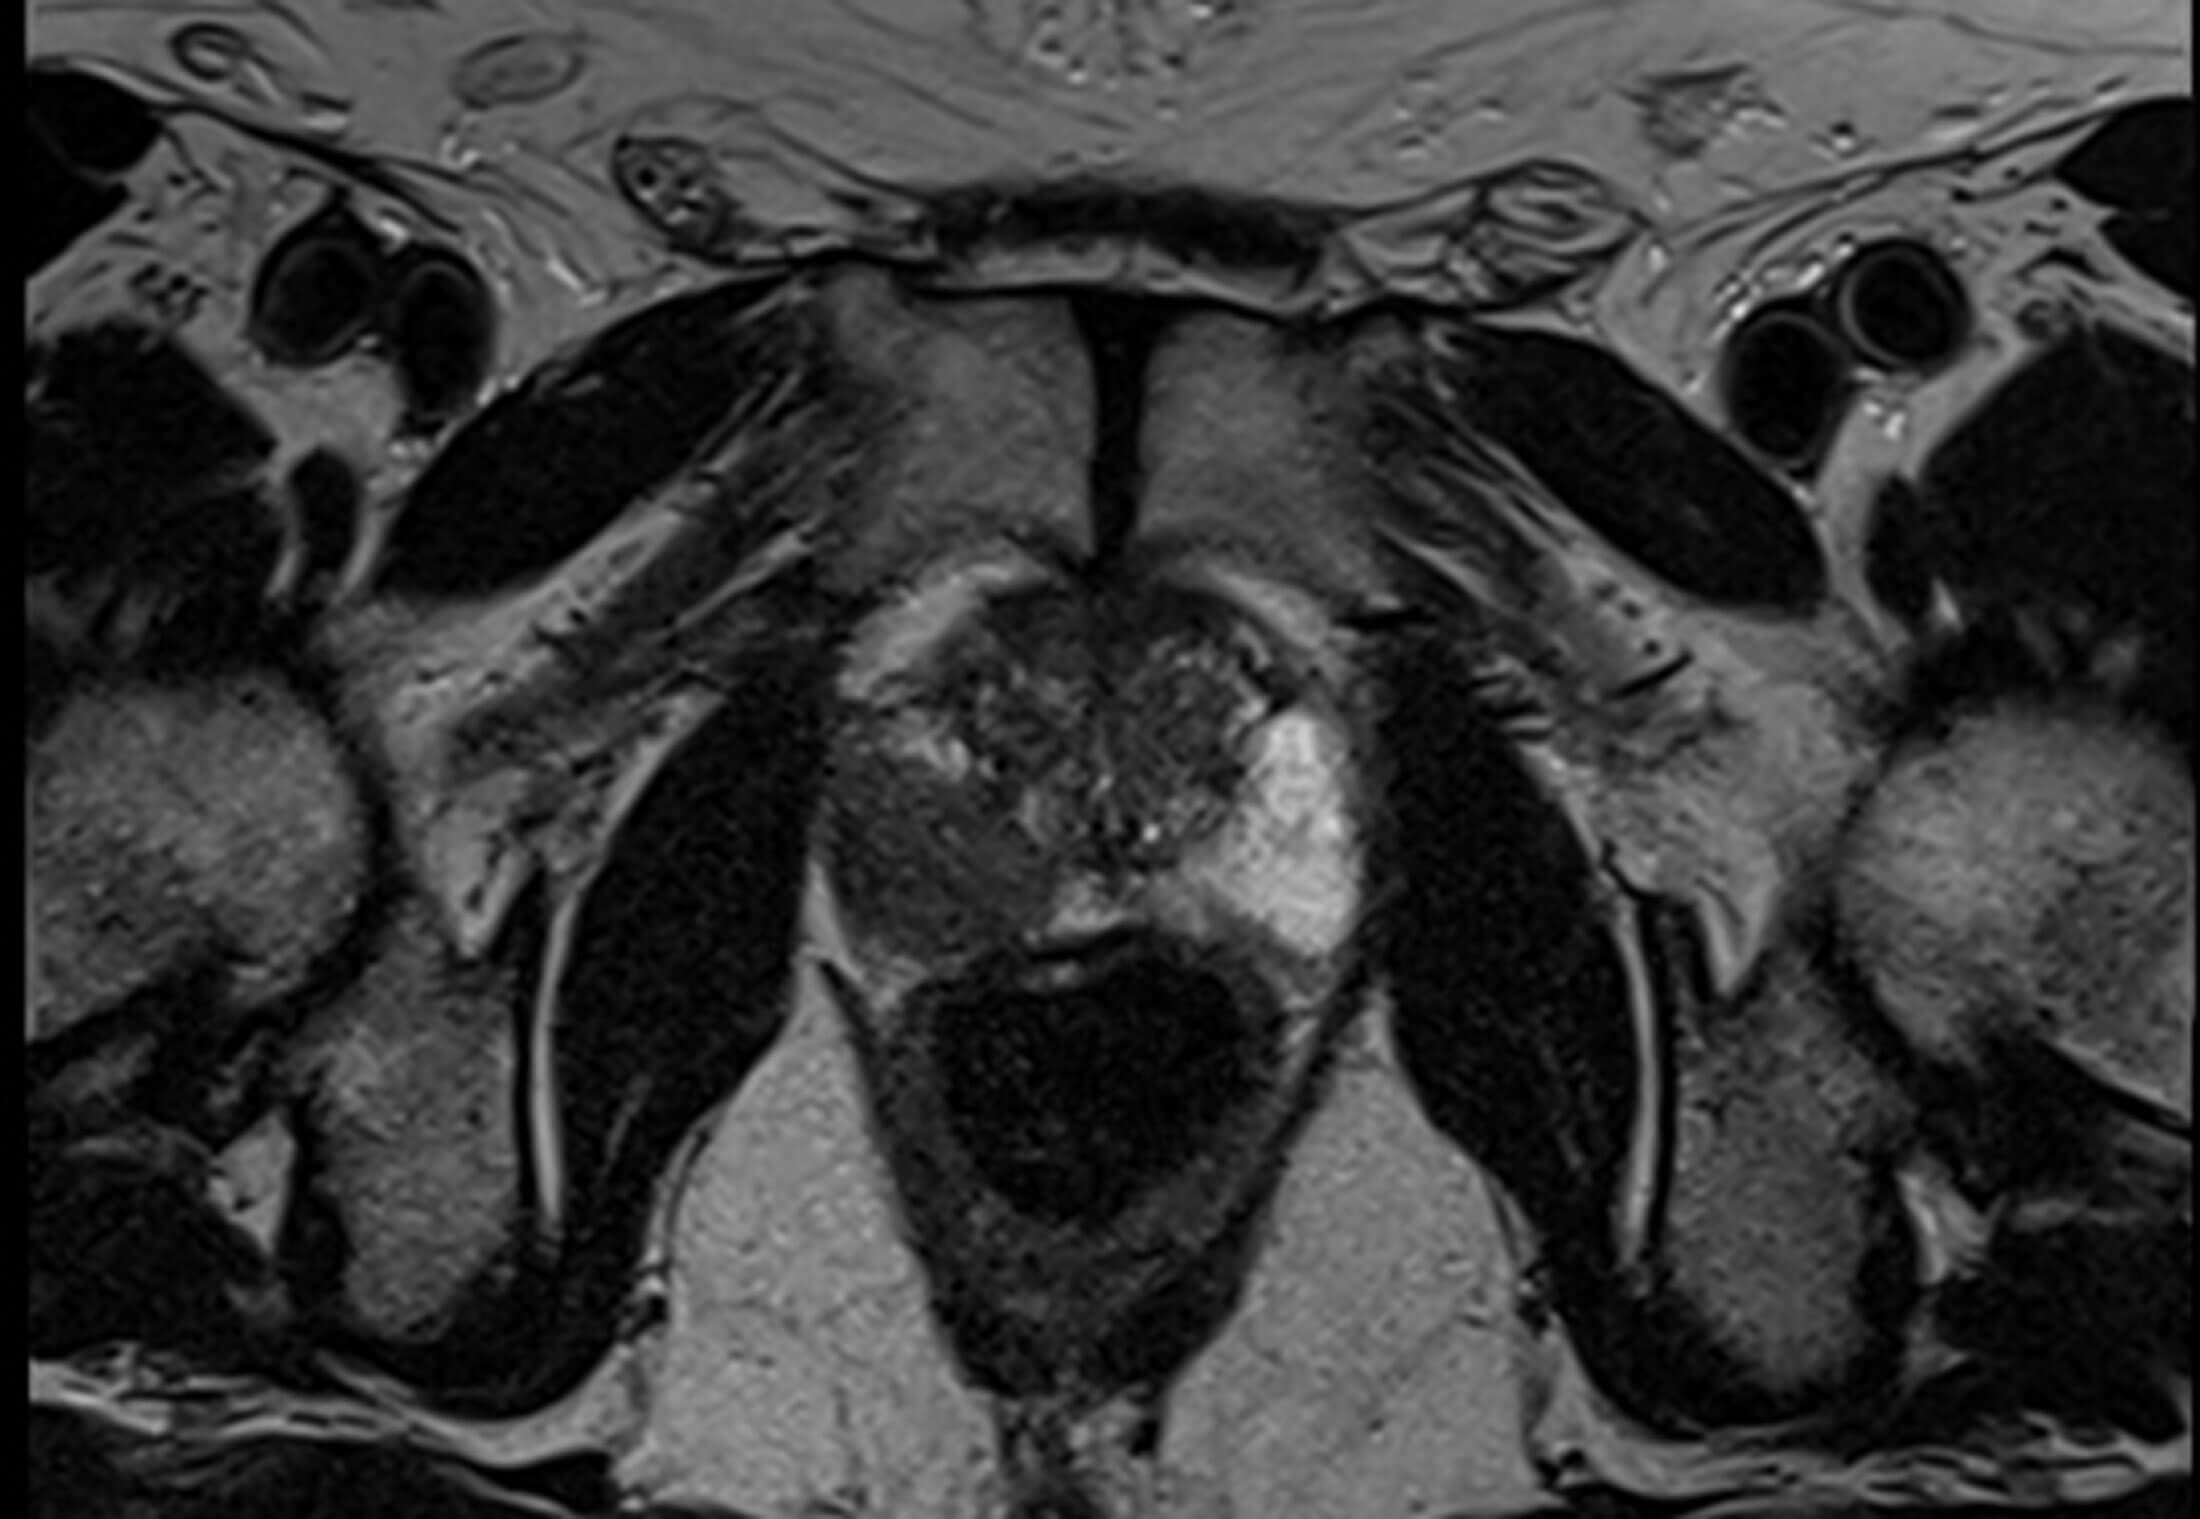

Figure 1.

1. Figure 1 is an axial T2 weighted MRI image. It shows an abnormal 3cm lesion in the mid-gland of the right peripheral zone, between 6 o’clock and 8 o’clock. It would be considered T2 N0 M0. Prostate cancer appears dark on T2 weighted imaging [1].